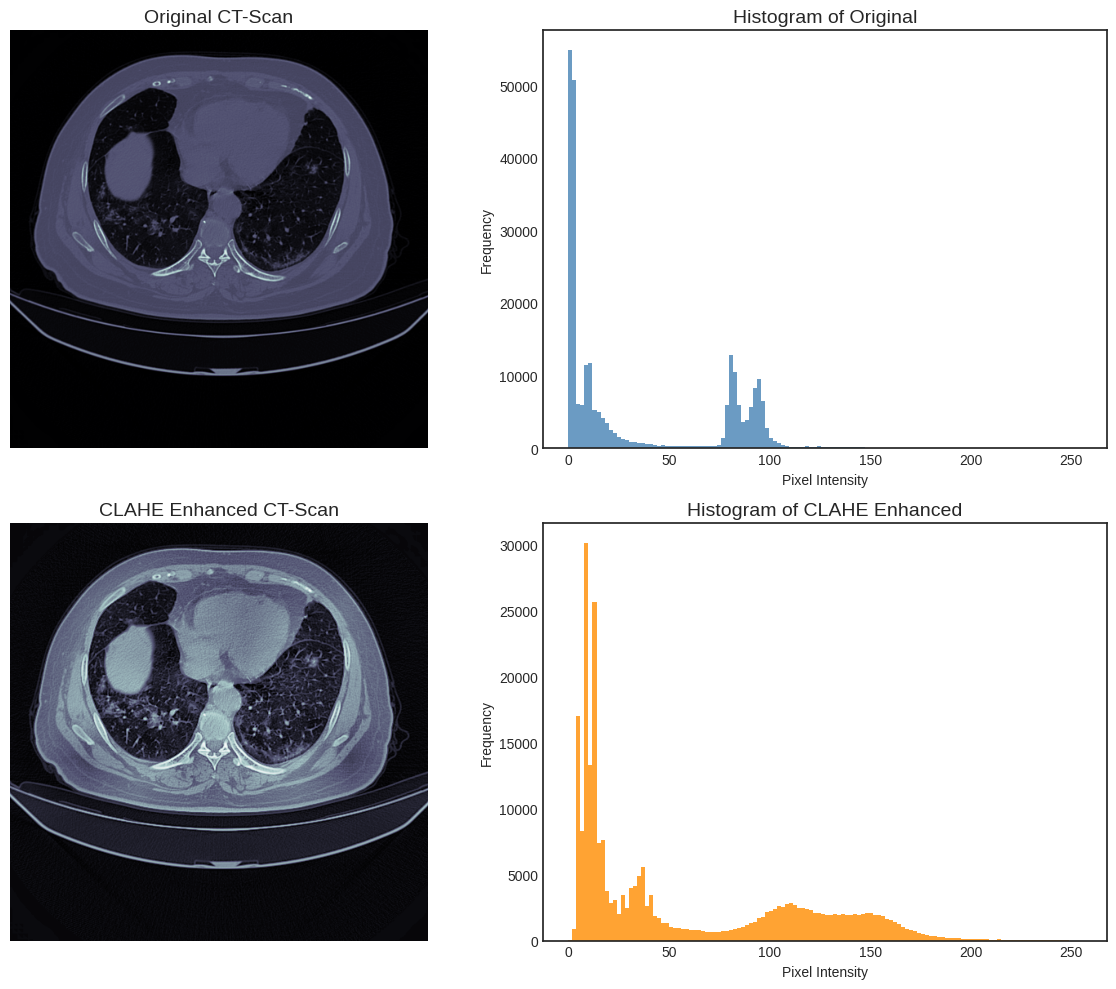

To prepare the images for classification, two key enhancement and extraction steps are applied. The first is Contrast Limited Adaptive Histogram Equalization (CLAHE). This technique improves the local contrast of the CT images, which is essential for highlighting subtle pathological features like ground-glass opacities. Unlike standard histogram equalization, CLAHE avoids over-amplifying noise in homogeneous regions by operating on small, distinct tile grids and limiting the contrast enhancement.

Figure 2 illustrates the effect of CLAHE on CT scans. The original CT image (top left) and its corresponding histogram (top right) show that most pixel intensities are clustered in narrow low-value ranges, limiting contrast between anatomical structures. After applying CLAHE (bottom left), the enhanced image exhibits improved visibility of lung details, while the corresponding histogram (bottom right) demonstrates a more balanced distribution of pixel intensities across the full dynamic range. This redistribution enhances local contrast and highlights subtle structural variations that are less discernible in the original scan.

Figure 2: Comparison of original and CLAHE-enhanced CT scans with corresponding histograms